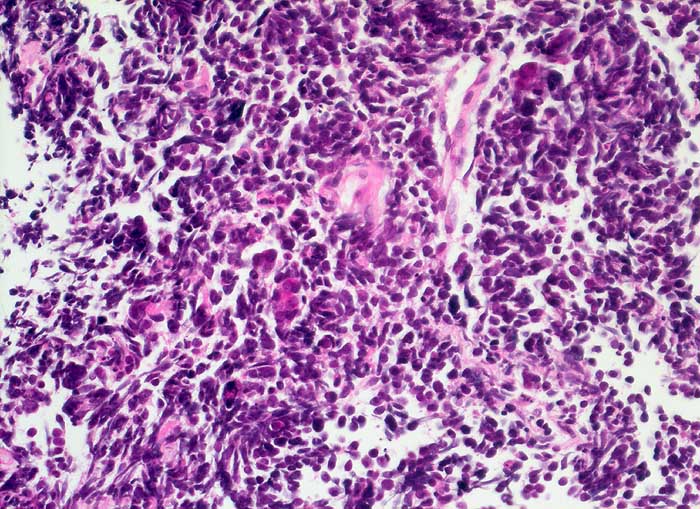

Kleinzelliges Karzinom

Lunge

Typischer Aspekt des kleinzelligen Tumors mit dicht gelagerten kleinen Tumorzellen mit fragilen Kernen und kaum erkennbarem Zytoplasma.

Totale Stenose des rechten Hauptbronchus mit Kompression der Vena Cava superior. Kleinzelliges Karzinom? Lymphom?

Histologie

400